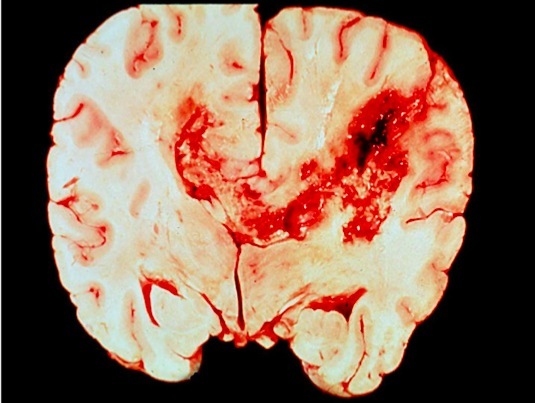

Intraparenchymal/intracerebral hemorrhage

C&C:

Vascular malformations

AVMs

– Greatest potential for hemorrhage

– High flow channels without arterial structure -> high calibre vessels in cortex where it should small calibre

– Rx: excision, endovascular occlusion, spray embolic agents